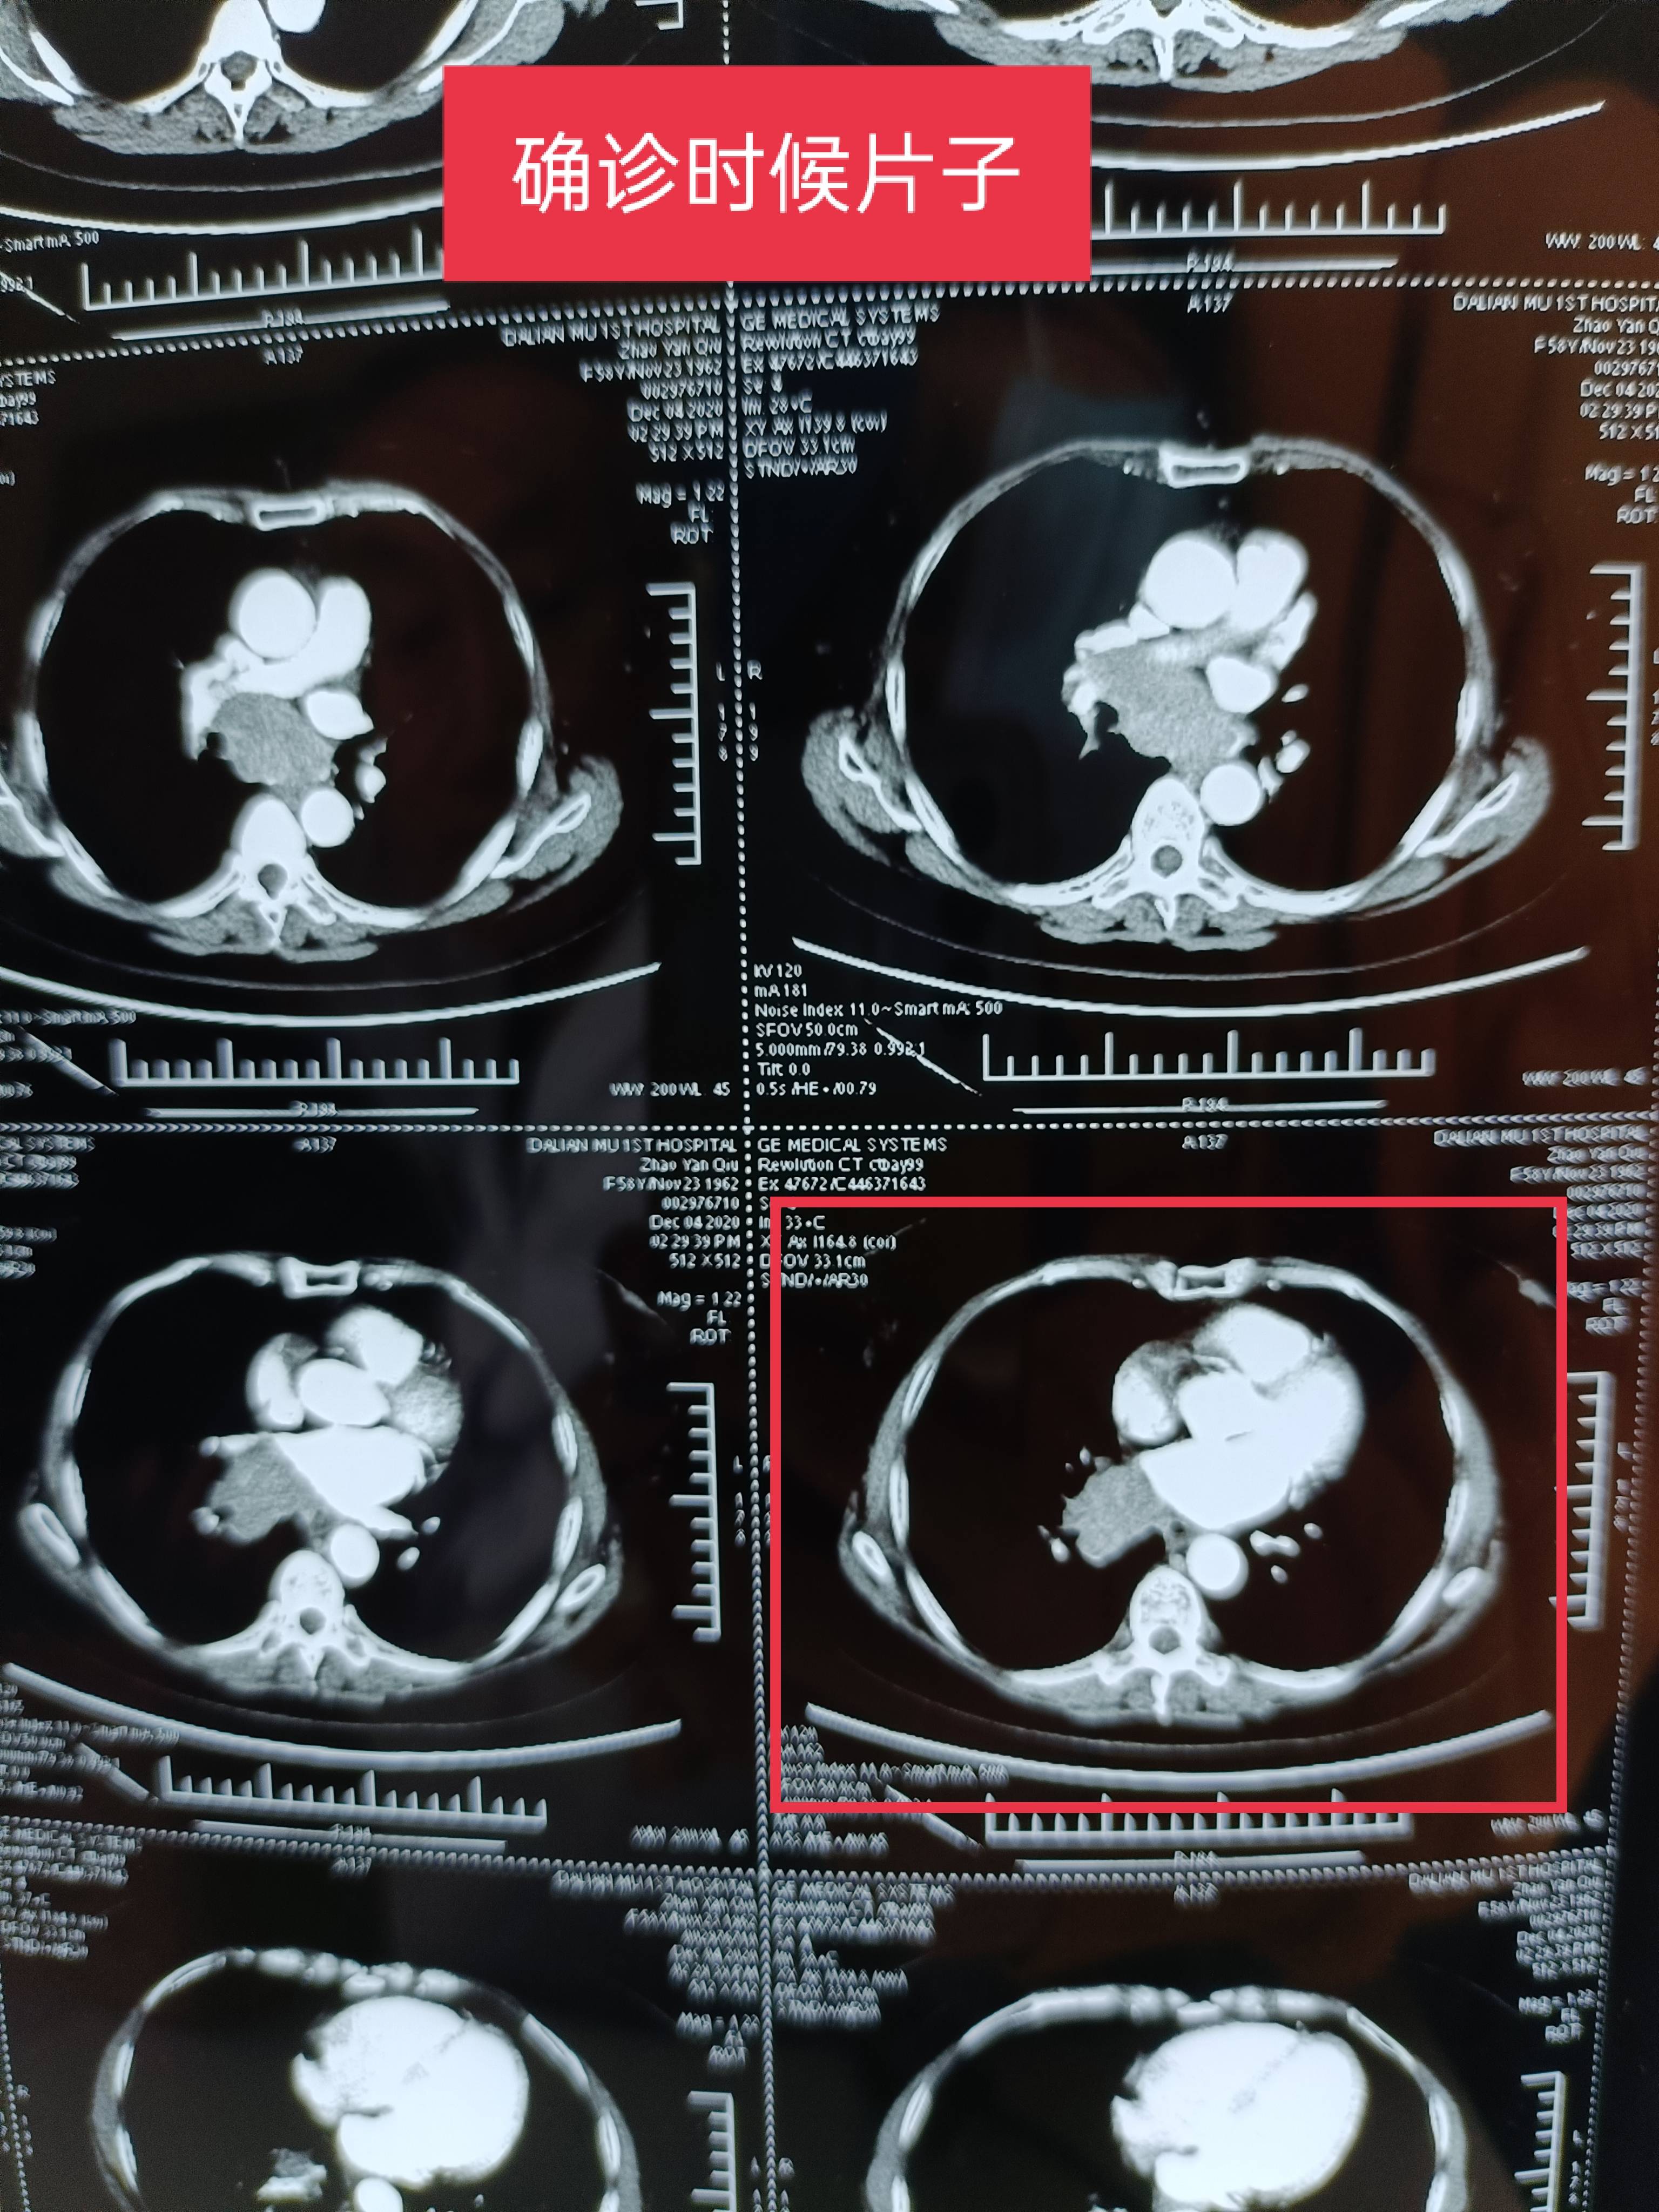

附上确诊到现在不确定复发的片子图,还有从开始到现在的肿标。